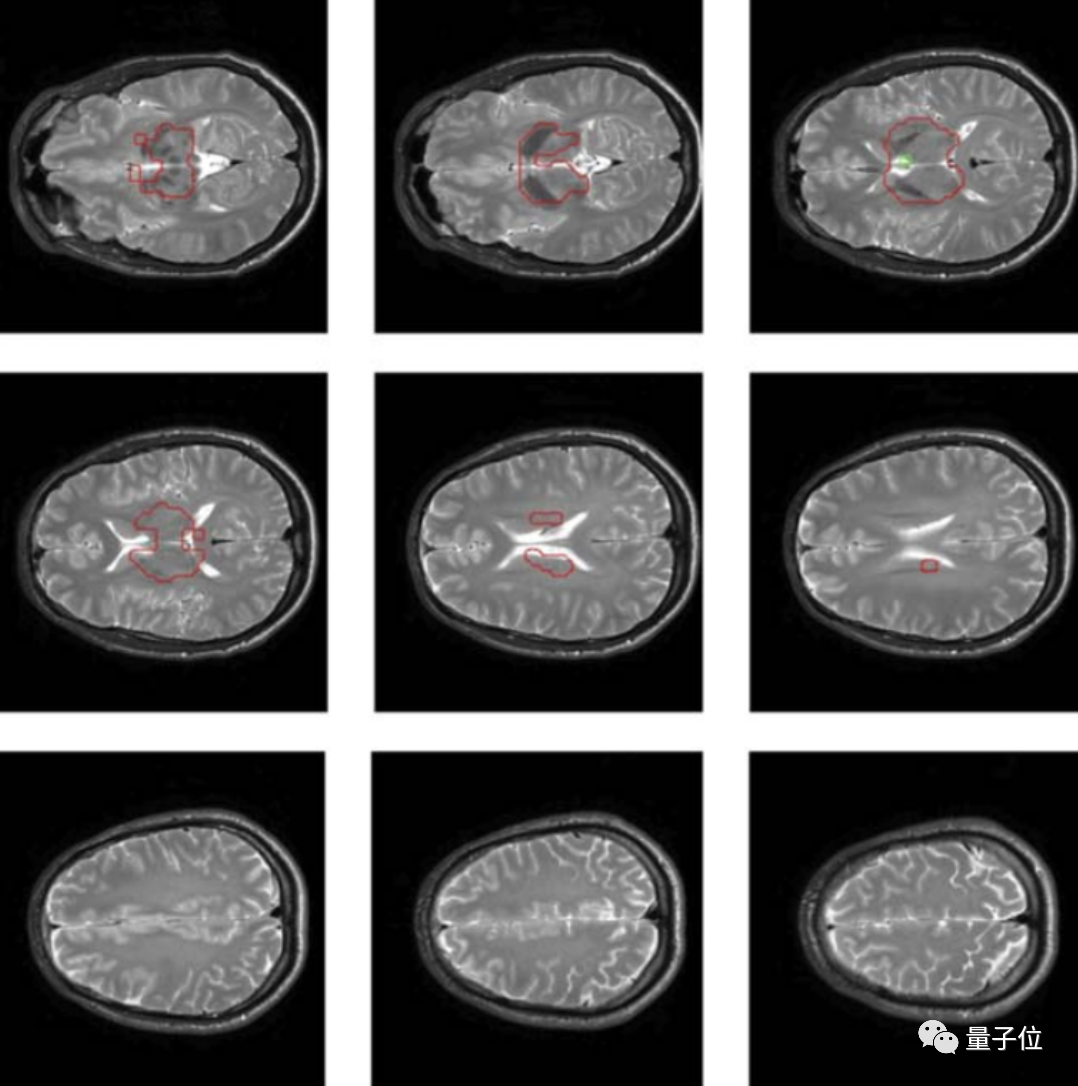

具体来说,这项研究采用了一种基于多量子相干的磁共振成像方法。

磁共振成像能基于核磁共振原理,检测构成物体原子核的情况,进而推断组成物质的分布、种类、数量、化学环境等,据此绘制成整个物体内部的结构图像。

通过这种方法,在测量了40个人(18~46岁之间)的大脑信号后,研究人员在大部分人的大脑区域中都测量出了一种诱发脑电信号。

这类信号有点像心跳诱发脑电位信号(HEPs,大脑感应心跳的信号),都依赖于大脑意识的产生,主要与短期记忆与意识感知相关。

然而正常来说,基于多量子相干的核磁共振根本没办法检测到诱发脑电信号,因为这些信号与任何经典的核磁共振信号都没有相关性。

对此研究人员推测,这一现象用量子纠缠解释是最合理的,进一步来说,这也意味着这些大脑功能与量子计算相关。